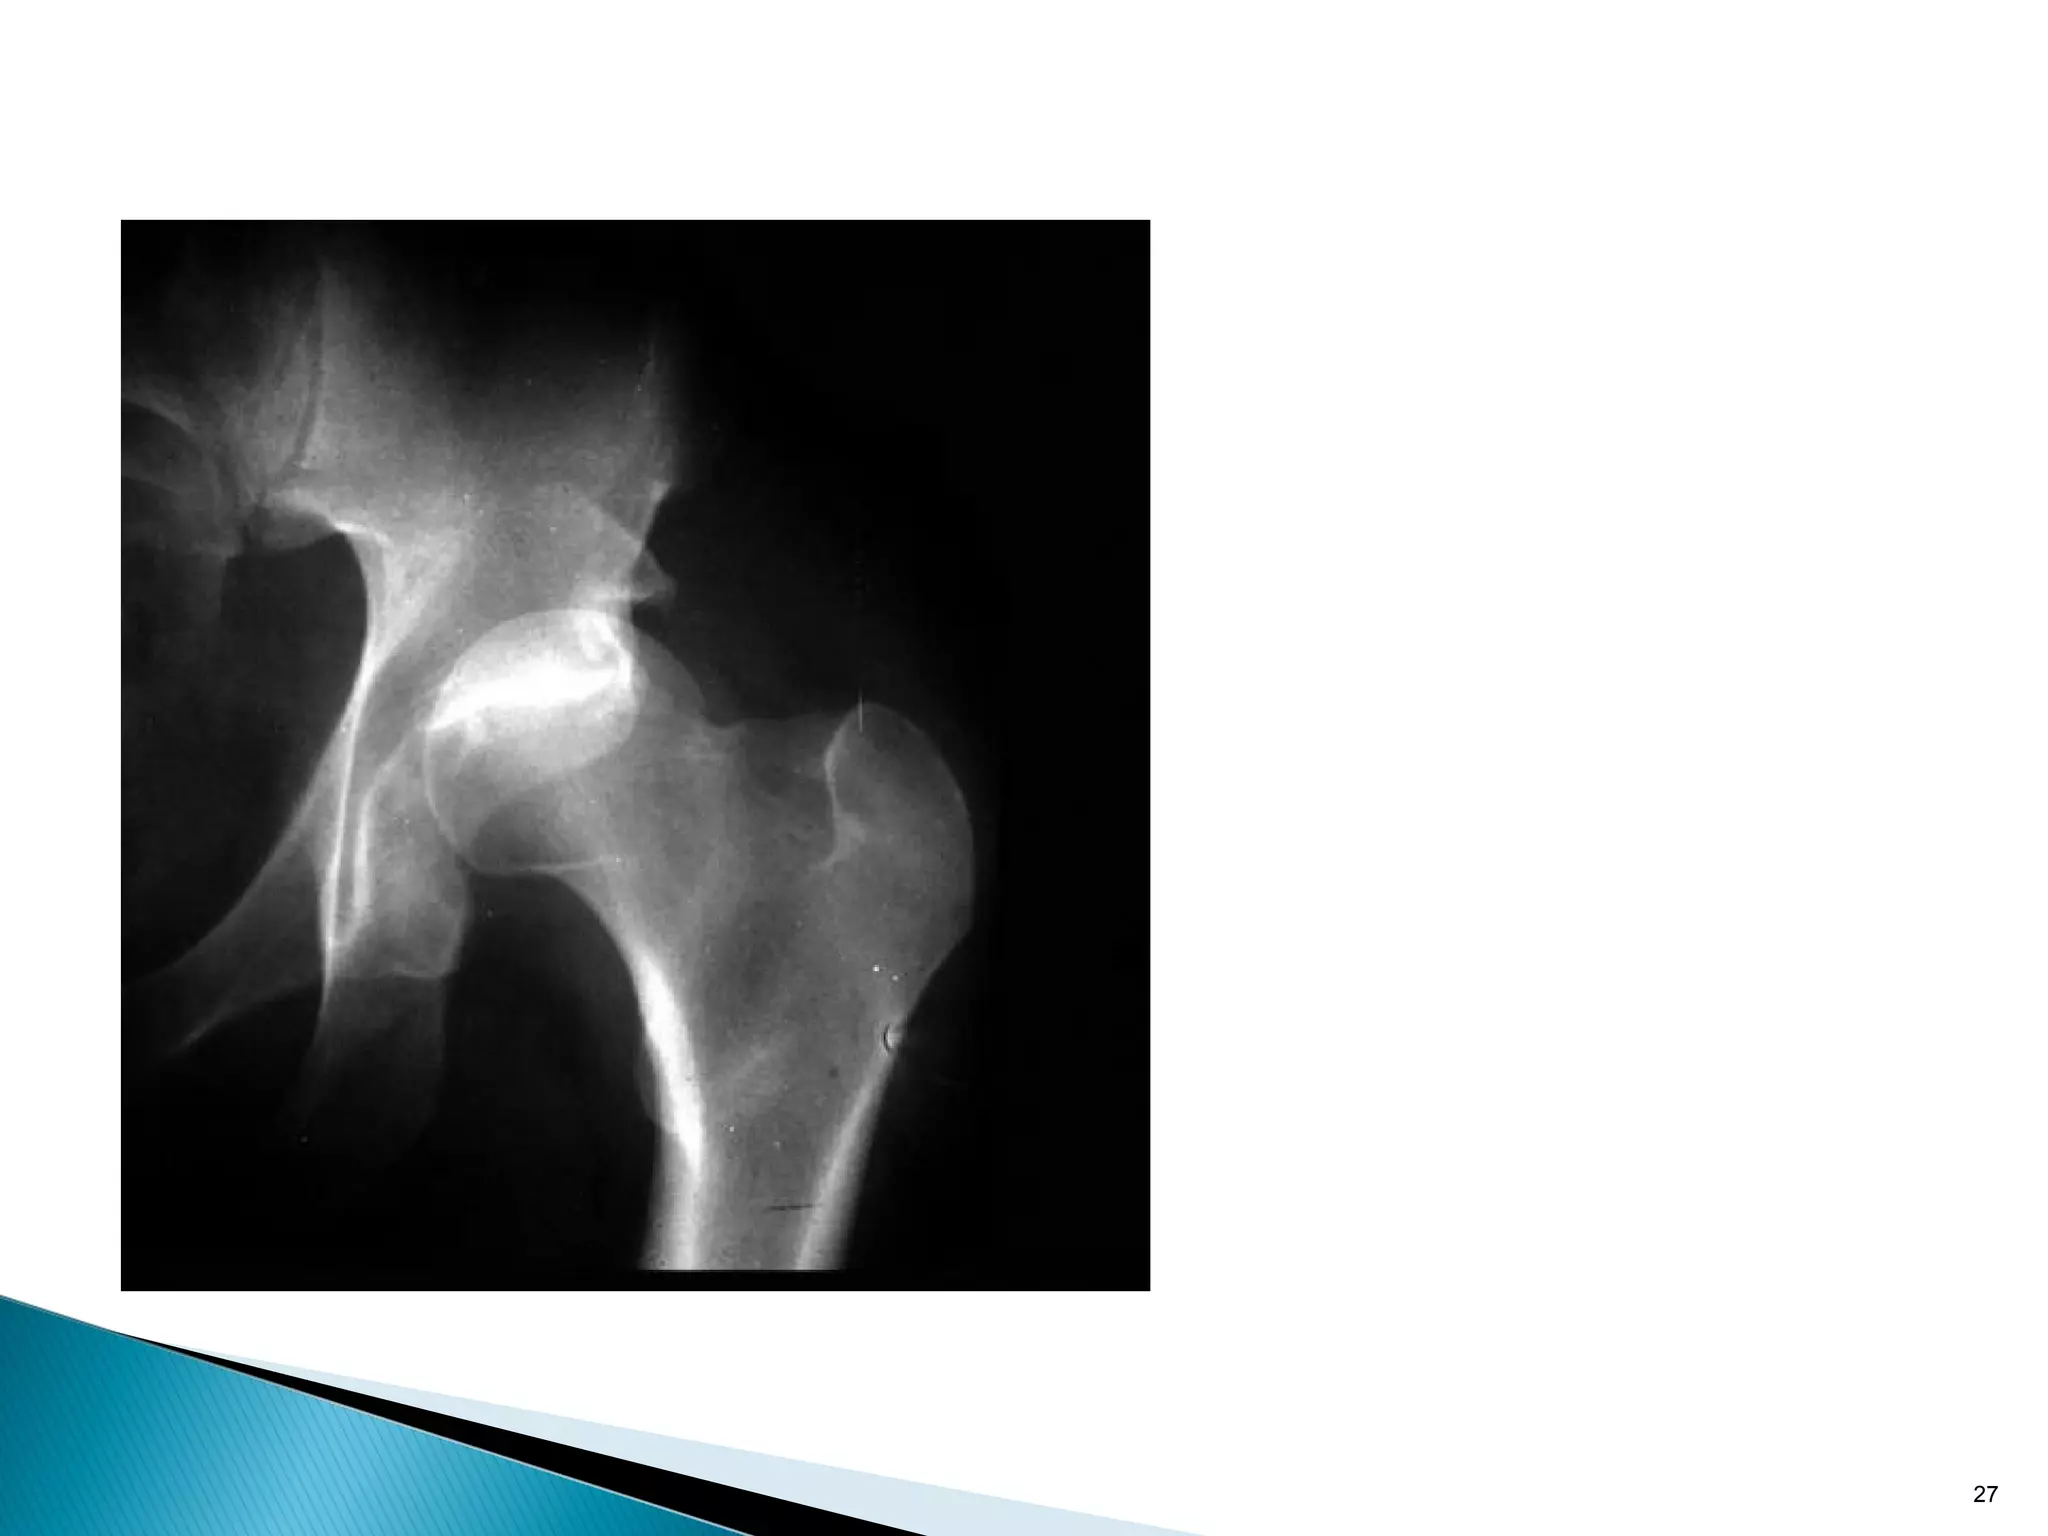

Absolute stability: tension band principle

In the eccentrically loaded femur the tension side is always

lateral.

A plate MUST be placed on convex (tension) side to counteract

distraction forces.

However there must also be a medial bony buttress, if

missing, the plate will break due to fatigue.

Plate on concave side distracts fracture

20 Absolute stability: tensionband principle In the eccentrically loaded femur the tension side is always lateral. A plate MUST be placed on convex (tension) side to counteract distraction forces. However there must also be a medial bony buttress, if missing, the plate will break due to fatigue.

21 Plate on concaveside distracts fracture Absolute stability: tension band principle